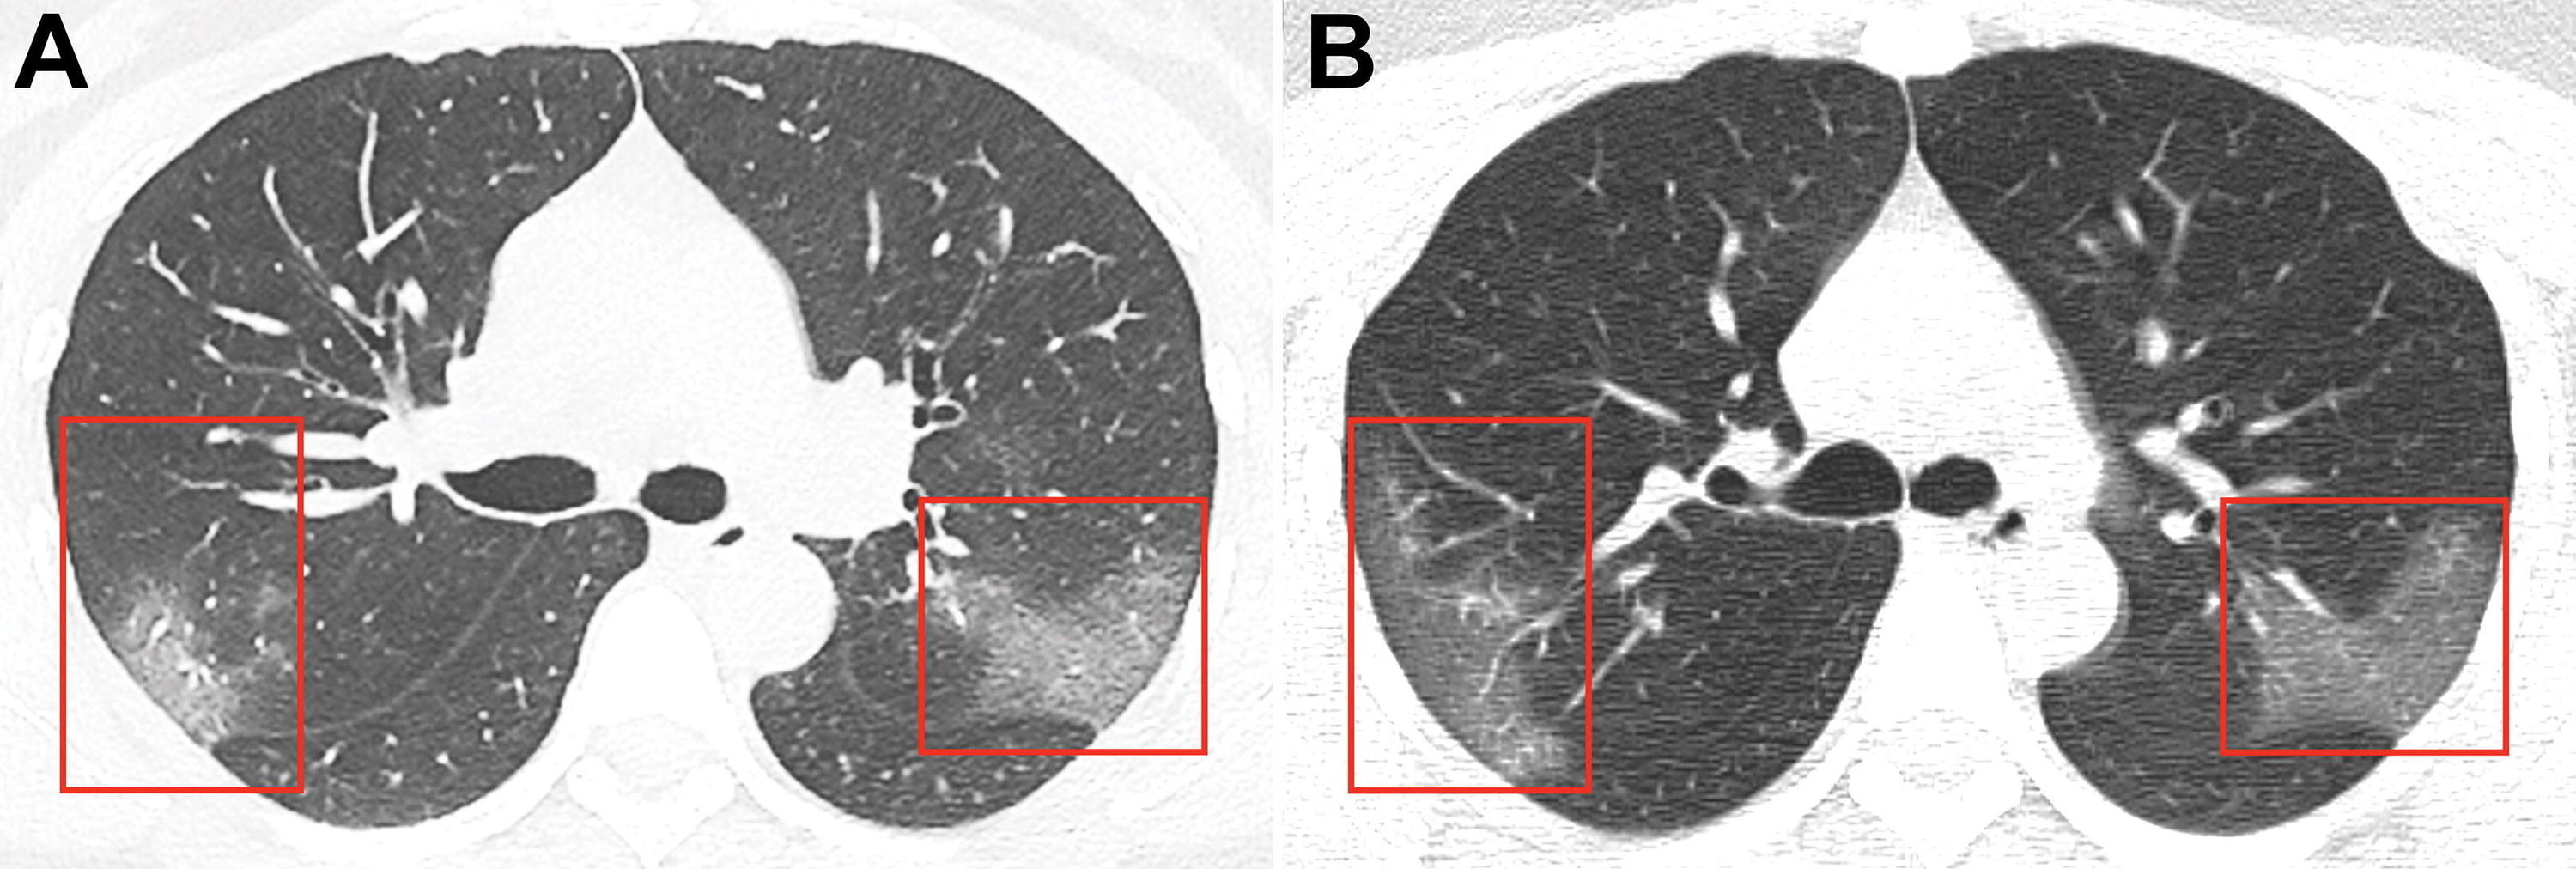

Trung Quốc công bố ảnh chụp lá phổi bị virus corona tàn phá. Hình ảnh chụp phổi của một bệnh nhân bị nhiễm coronavirus 2019 nCoV gây chấn động.

Ảnh chụp lá phổi bị ảnh hưởng bởi virus corona.

Hình ảnh công bố trên tạp chí Radiology thu được bằng cách chụp cắt lớp vi tính lá phổi của người phụ nữ 33 tuổi nhập viện ở thành phố Lan Châu (Trung Quốc) khi sốt với thân nhiệt 39°C và ho suốt 5 ngày.

Trong bức ảnh đầu tiên có thể thấy vùng mờ như khói mà thuật ngữ X-quang gọi là "hiệu ứng kính mờ". Lần chụp thứ hai, vào ba ngày sau, đã thấy rằng khu vực bị tổn thương đang lan rộng.

"Dựa trên cơ sở đặc điểm dịch tễ học, các biểu hiện lâm sàng, ảnh chụp vùng ngực và dữ liệu phòng thí nghiệm, bác sĩ đã cho chẩn đoán bệnh viêm phổi cấp 2019-nСоV", - bài công bố cho biết.Coronavirus 2019-nCoV.